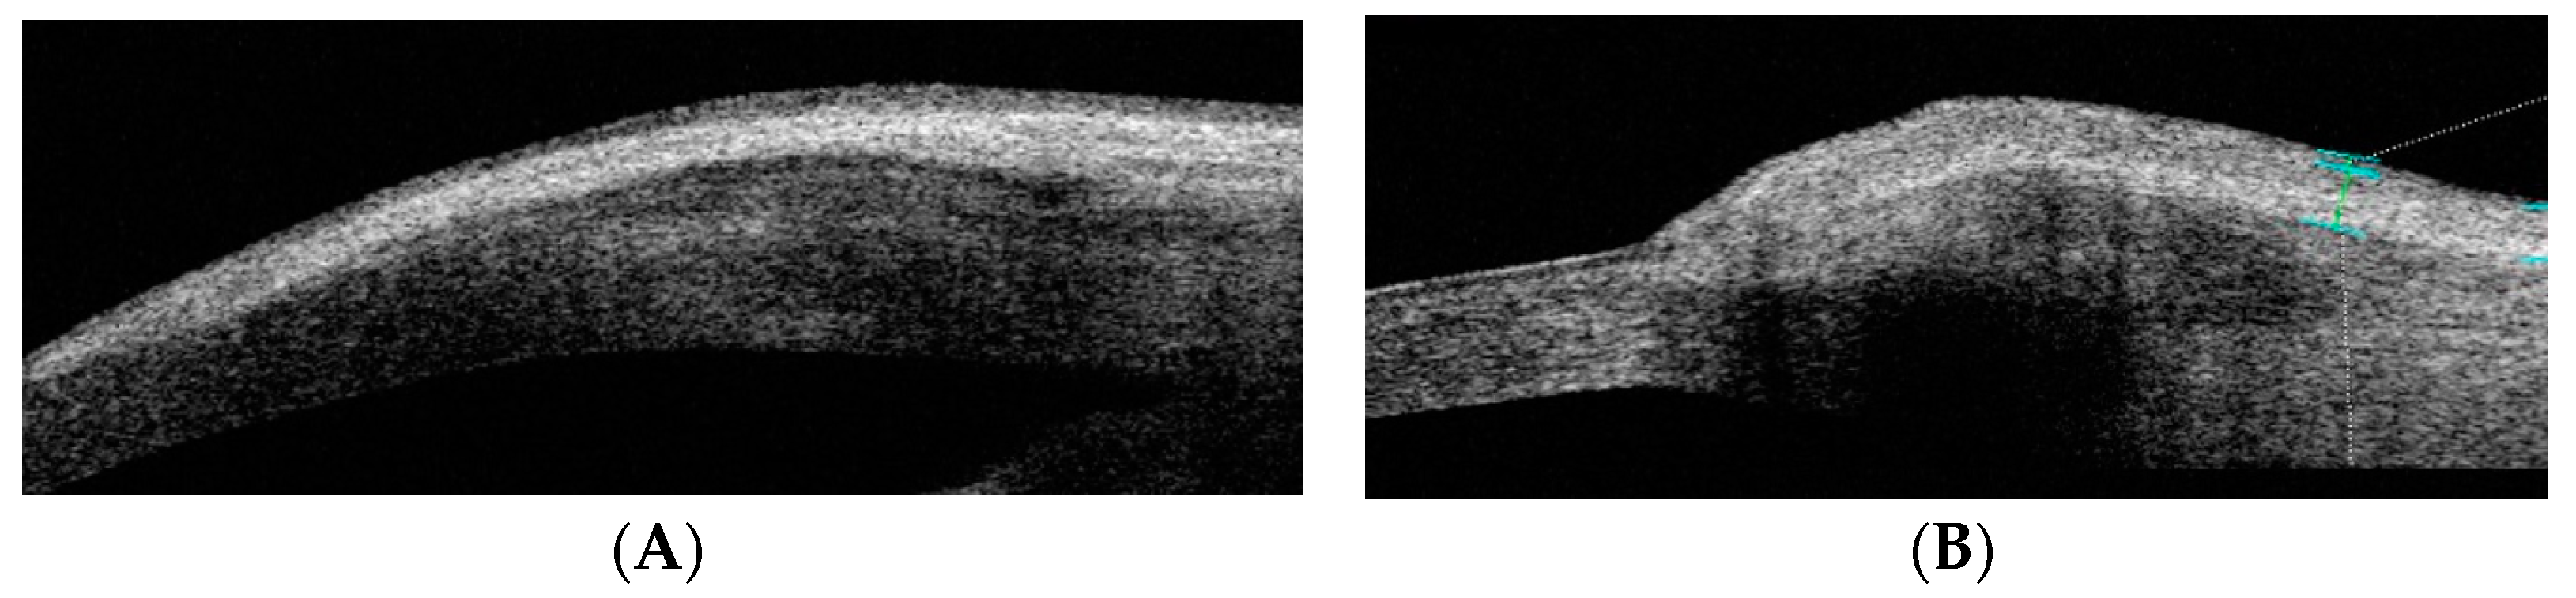

The following 10 pterygium anatomical parameters were measured in millimeters using AS-OCT: limbus thickness (LimbusT), central pterygium thickness (CentreT), head pterygium thickness (HeadT), horizontal corneal invasion (Horizontal Corneal Inv), epithelial thickness at 1 mm (EpitT1mm), stromal thickness at 1 mm (stromT1mm), total thickness at 1 mm (TotalT1mm), total thickness at 2 mm (TotalT2mm), total thickness at 3 mm (TotalT3mm), and pterygium type (nodular or flat) (Figure 1).

Figure 1. AS-OCT image of the tomographic classification of pterygium as flat or nodular. (A) OCT-SA image of flat pterygium: the shape of the ocular surface contour is not altered. (B) OCT-SA image of flat pterygium: the subepithelial mass of the pterygium is seen to cause a convex change in the curvature of the ocular surface of the limbus.